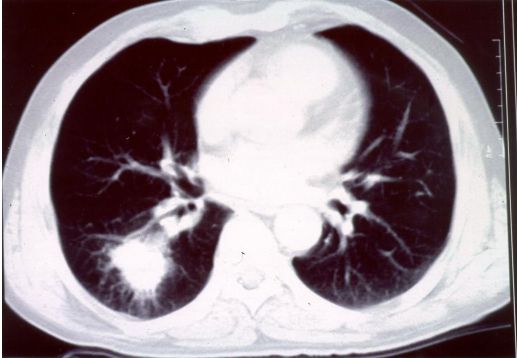

13. 39歲男性有多重性伴侶,因持續發燒及體重減輕3公斤,而且逐漸感到呼吸困難而入院,身體檢查發現口腔有白色珠菌 (Candida)感染,胸腔 X光如圖35 ,血液檢查結果: HIV Test :陽性、血液淋巴球比率: 8%、 CD3:34% 、CD4:0.2%、 CD8:36% 、CD19:4%,肺部灌洗液檢出囊胞蟲(Pneumocystis carinii),下列敘述何者為真?a. 囊胞蟲肺炎 ( Pneumocystis carinii pneumonia ) 典型表現為兩側肺門旁之浸潤,很快迅速進展成瀰漫性兩側肺部浸潤b. AIDS合併囊胞蟲肺炎患者的死亡率為單獨感染囊孢蟲肺炎者之三倍c. 所有囊胞蟲肺炎患者均需住院治療d. 大部HIV合併囊胞蟲肺炎病患的症狀均為突發性咳嗽,高燒而無呼吸困難症症狀e. Trimethoprium-Sulfamethoxazole仍為治療及預防囊蟲肺炎之首選藥物